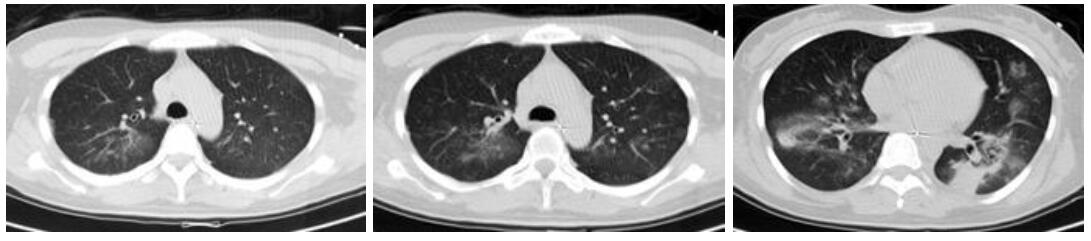

病例2,女,55岁,有鸽子喂养史,近半个月来咳嗽发热,咳剧时伴胸闷气喘,活动后加重,近1周出现纳差,伴呕吐、腹泻。入院查体:体温38 ℃,脉搏126次/min,呼吸32次/min,血压91/48 mmHg。神清,无皮疹,浅表淋巴结无肿大,右肺闻及湿啰音,心律齐,未闻及杂音,肝脾肋下未触及。胸部CT示右肺大片实变,见图 3A。甲、乙型流感抗原检测阴性。入院诊断:重症社区获得性肺炎。予无创机械通气,美罗培南+莫西沙星抗感染,奥司他韦抗病毒,入院第3天查胸片示两肺斑片状模糊影(图 3B),予气管插管辅助通气,查PCT 7.88 ng/mL。改用阿奇霉素+万古霉素抗感染。入院第8天行肺泡灌洗液mNGS检测:鹦鹉热衣原体(序列数314),鲍曼不动杆菌(序列数23),改舒普深+替加环素治疗。经治疗后,患者症状无明显好转,并发严重上消化道出血,入院第13天查胸片示病灶范围扩大(见图 3C),因病情危重,生命体征不平稳未行CT复查,患者病情进行性恶化,治疗14 d后死亡。

| A:入院时胸部CT,右肺大片实变;B:入院第3天床边胸片,两肺斑片状模糊影;C:入院第13天床边胸片,两肺斑片状模糊影,较前有进展 图 3 病例2胸部检查结果 |